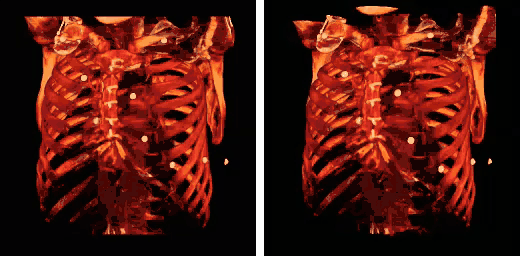

The influence on volume rendering of various shading settings is shown below:

3D VR shading comparison.

The shading settings used for the above images are as follows:

Image Ambient Coefficient Diffuse Coefficient Specular Coefficient Specular Power

Top Left

0.15

0.9

0.3

15.0

Top Middle

0.75

Top Right

0.1

Bottom Left

1.2

Bottom Middle

1.0

Bottom Right

0.6